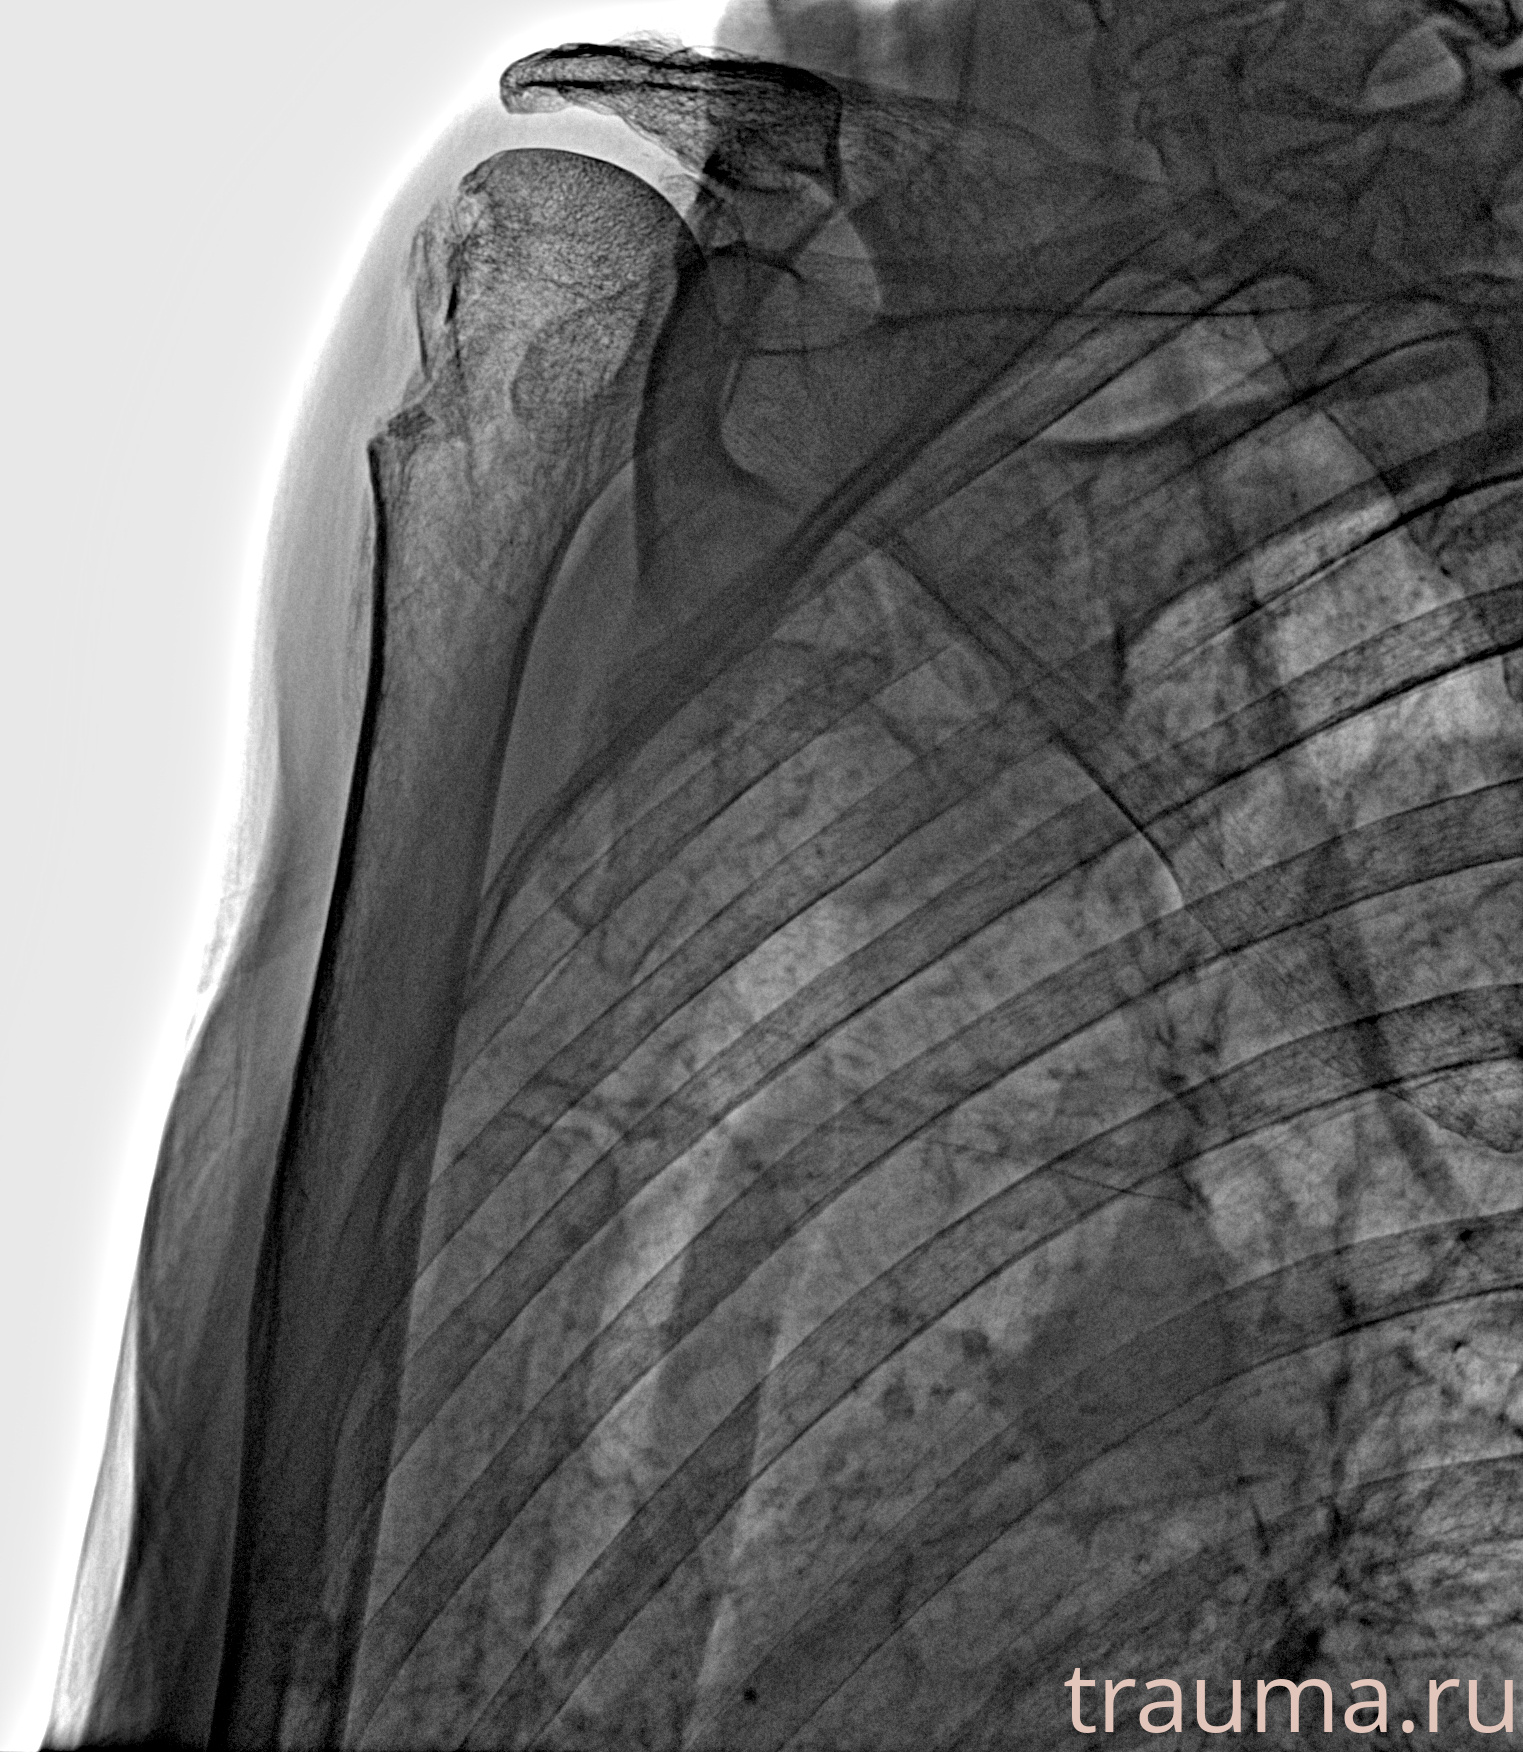

Рентгенограммы

Рентген на дому: по вашему адресу приезжает врач-рентгенолог, травматолог-ортопед с мобильным рентгеновским аппаратом, проводит диагностику травмы или заболевания, делает необходимые рентгенограммы, дает рекомендации по дальнейшему лечению. Получить качественные снимки в домашних условиях возможно благодаря уникальной методике, разработанной МосРентген Центром для института  Склифосовского